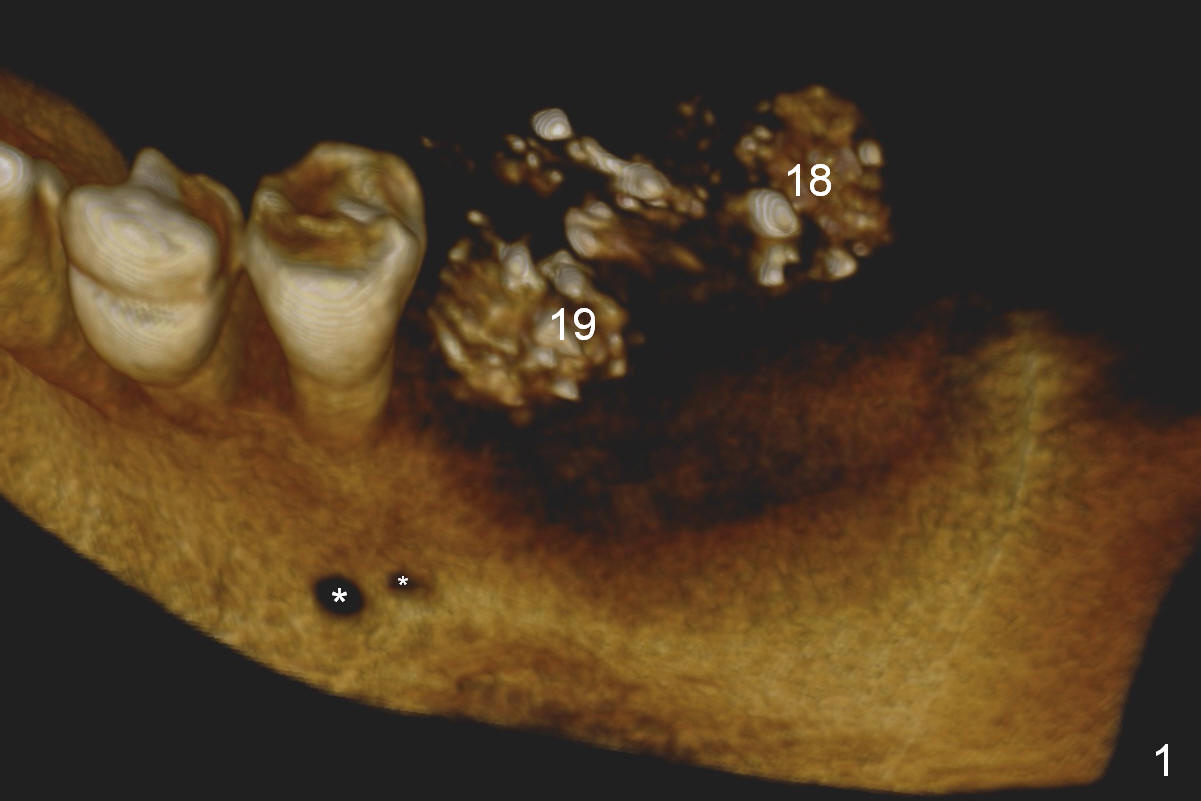

CBCT 3-D image taken with scan stents at the sites of #18 and 19 shows 2 Mental Foramina (Fig.1 *) in the left mandible.  Both sagittal (Fig.2) and coronal (Fig.3) sections show low density at the crest of #19 of a 55-year-old man (arrowheads).  The crest is also narrow.  After making an initial osteotomy through the stent (Fig.4 red arrow), remove the latter (Fig.5).  Ridge split is initiated with wheel saws (Fig.6 blue line).  The osteotomy is enlarged with bone expanders (Fig.7 green circle) with ridge split (blue lines).  Finally an implant is placed (Fig.8 pink circle) with placement of bone graft in the space of the ridge split (yellow circles).

Without ridge split, the ridge top has to be trimmed (Fig.9 black area) to hold a 3 mm shorter implant (Fig.10,11).